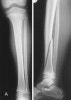

유아기 골절(Toddler’s fracture)

An undisplaced spinal fracture of the tibia.